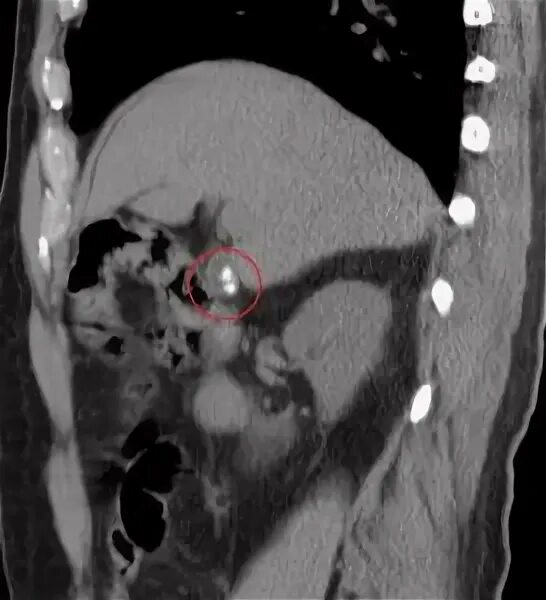

Камни в желчном мрт